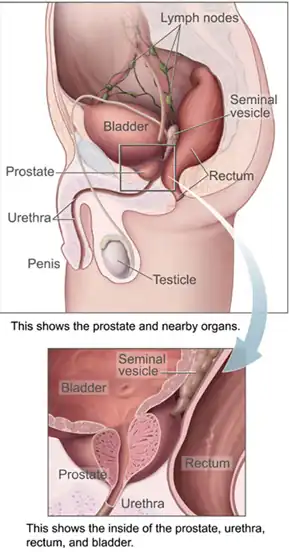

Male pelvic organs seen from right side.

Male pelvic organs seen from right side.